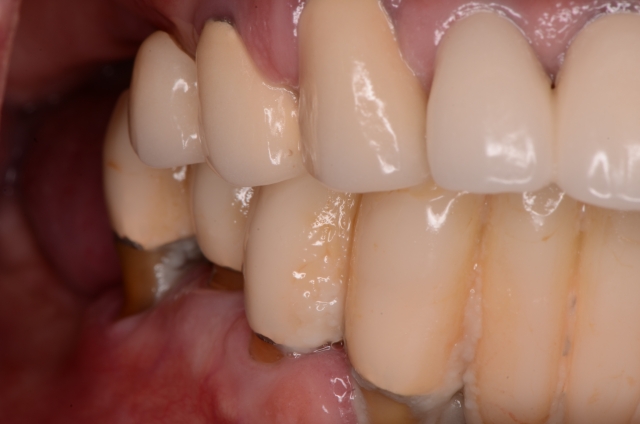

Photography is the linchpin of the entire co-discovery process. We take six pictures in every new case. Spear teaches that these are the six images that will improve case acceptance. Here’s an example:

Rampant root caries, extreme worn dentition and the corrosive effects of GERD are all effectively demonstrated with these photos. These photos get the ball rolling on patients requiring more comprehensive treatments due to a terminal dentition.